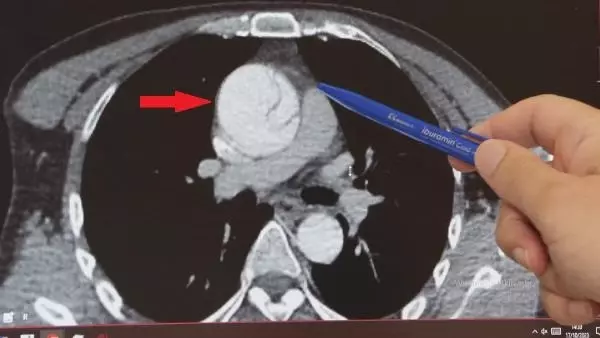

Daha önce hiçbir sağlık sorunu olmayan 41 yaşındaki Mustafa Turan, birkaç hafta önce arkadaşlarıyla ayak üstü sohbet ederken "Göğsümde yırtılırcasına bir ağrı başladı" diyerek fenalaştı ve acile kaldırıldı. Kalp ekosu çekildi çeşitli tahliller yapıldı ancak her şey normal görünüyordu. Ağrılarının midesinden olabileceği düşünüldü ve gerekli tedavileri verilip taburcu edildi. Şiddetli ağrıları ertesi gün de devam eden Turan, gece 02.00 sularında Göztepe Süleyman Yalçın Şehir Hastanesi acil servisine başvurdu. Acildeki doktorun şüphelenmesi üzerine tekrar EKO çekildi, abdominal aort anevrizması (AAA) nedeniyle karın bölgesinden geçen aort damarında yırtık olduğu tespit edildi. Normalde 2 santim çapında olması gereken aort damarı anevrizma (balonlaşma) nedeniyle genişleyerek neredeyse 3 katına ulaşmış, damar duvarında yırtığa neden olmuştu. Hayati riski olduğu anlaşılan Turan, kalp damar cerrahisi ekibi tarafından acilen ameliyata alındı.

Göztepe Süleyman Yalçın şehir Hastanesi Kalp Damar Cerrahisi Klinik Şefi Prof. Dr. Ebuzer Aydın, "Arkadaşlarıyla konuşurken böyle bir boğazında düğümlenme şikayeti oluyor. Bunun üzerine ambulansla acile geliyor. Tetkikleri yapılıyor, daha çok mide şikayetleri düşünülerek o yönde tetkikler yapılıyor ve tedavisi verilip gönderiliyor. Ağrıları geçmeyince tekrar acile geliyor, acildeki doktor arkadaşlarımızın dikkati ve özeni sayesinde ayrıntılı tetkik yapılıyor ve bu sırada aort diseksiyonu olduğu görülüyor. Bize konsülte edildi ve hızlı bir şekilde ameliyathanemizi ayarladık, acilen ameliyata aldık" dedi.

Aort anevrizmasının çoğunlukla sessiz ilerlediğini kaydeden Prof. Dr. Aydın, genellikle başka tetkikler yapılırken tesadüfen teşhis edilen hastalıkta en önemli şeyin, aort damarında yırtık meydana geldikten sonra kaybedilen her 1 saat için ölüm riskinin yüzde 1 artması olduğunu vurguladı. Aydın, "Acil ameliyatla, elektif (planlı) ameliyat arasında ölüm riski açısından, ameliyattaki diğer riskler ve hastaya getirdiği başka tehlikeler açısından çok ciddi farklar var. Her 1 saat için ölüm riski yüzde 1 artar. Bu hastalar çoğunlukla kanama ve getirdiği bir takım diğer komplikasyonlarla kaybedilir. Planlı ameliyatlarda ölüm riski yaklaşık yüzde 5 iken diseksiyon meydana geldiğinde bu risk yüzde 20-25'lere kadar çıkabiliyor. Yani planlı bir anevrizma ameliyatı ile diseksiyon ameliyatı arasında 4-5 kat fark var" ifadelerini kullandı.